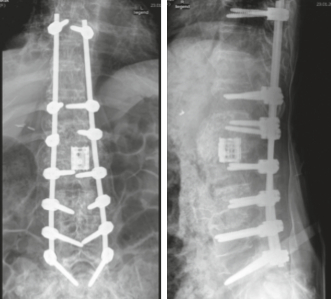

Auswirkungen auf die Wirbelsäule

Eine Neuroarthropathie an der Wirbelsäule endet praktisch immer in einer wirbelsäulenchirurgischen Stabilisation. Manchmal, so Koch und Geng, muss der zerstörte Bereich durch Transplantation von Knochen oder Implantation eines Cages (Platzhalters) komplett überbrückt werden. Häufig muss die Wirbelsäule bis zum Becken/Kreuzbein hinunter stabilisiert werden.